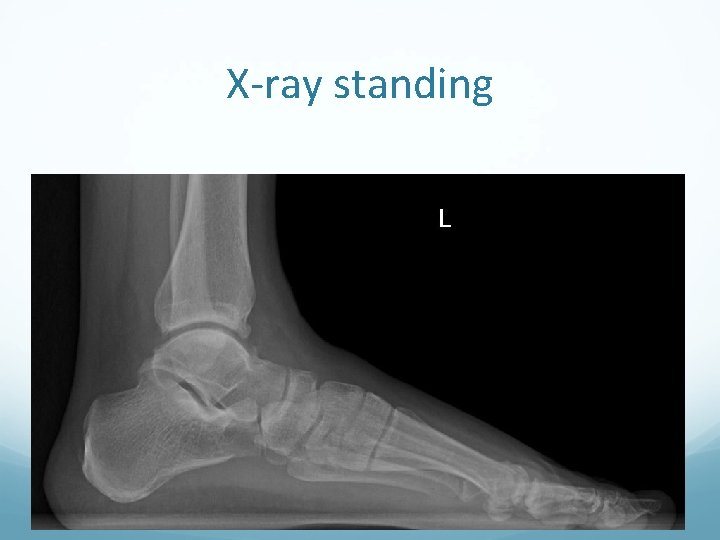

X-ray standing